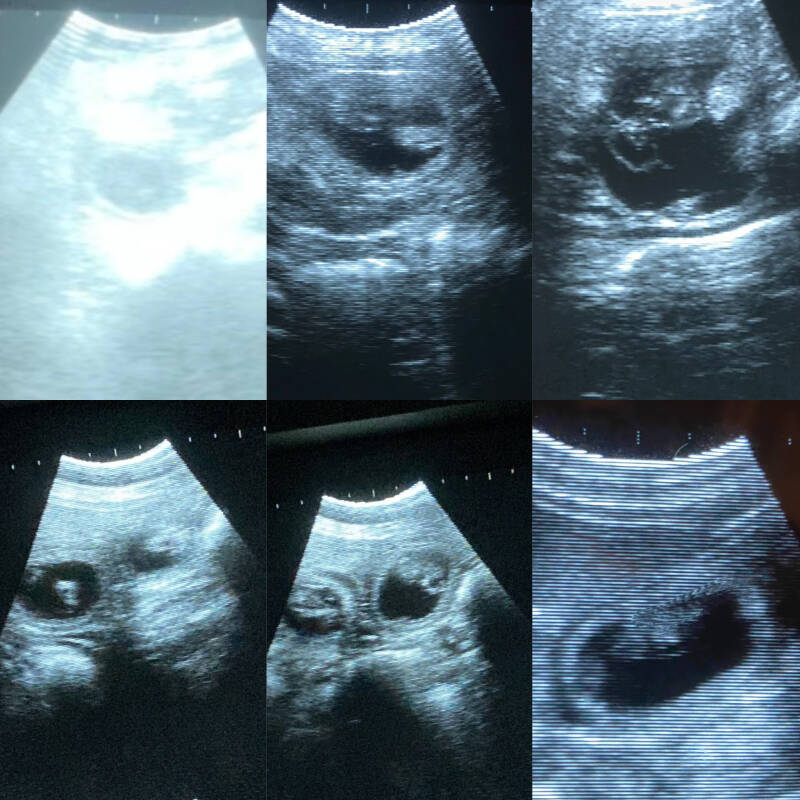

Dracht echo

vanaf heden ook mogelijk om hier met 28 dagen een echo te laten maken.

Teef drachtig  €50

Als de teef niet drachtig blijkt te zijn betaald u slechts €25

Op locatie is niet meer mogelijk.